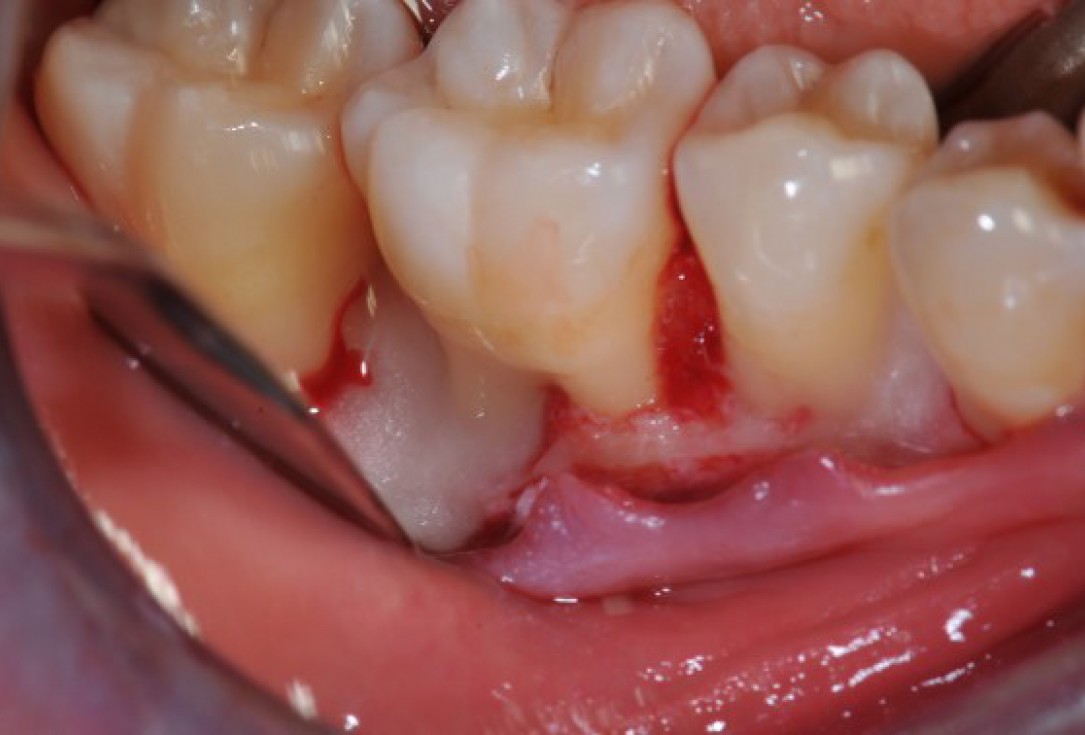

02/22 - Pre-surgical clinical situation, lingual view.

Deep intrabony defects treated using Straumann® Emdogain® - Dr. M. Stefanini